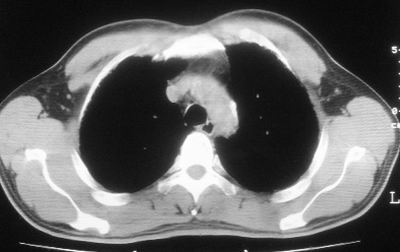

患者,男,44岁,糖尿病4年余,近期消瘦、乏力。化验检查:总胆红素26.33(参考值:5.1-17.2u mol/l),直接胆红素:6.4(参考值:0-4.3u mol/l),谷-丙转氨酶(alt):843(参考值:<40u/l),hbsag(+),抗hbs(-),hbeag(-),抗-hbe(+),抗-hbc(+)。

双肺散在小结节影,考虑粟粒性肺结核.肺窗薄扫会更好看些.

双肺外侧带胸膜下可见网状阴影,考虑轻度肺间质纤维化。

双肺纹理增强并可见网格状影达外带,考虑双肺感染并轻度间质纤维化

肺间质纤维化并肺部感染,结合不能排出,毕竟糖尿病人易合并之,建议结合ppd检查或hrct进一步扫描。